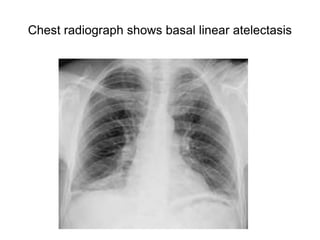

Chest radiograph shows basal linear atelectasis

• Plate atelectasis

• linear subsegmental atelectatic shadows

at the lung bases

Plate (linear) atelectasis

• Is a focal area of subsegmental atelectasis with a linear

configuration, almost always extending to the pleura.

• Also known as discoid or plate like atelectasis.

• It is commonly horizontal but sometimes oblique or

vertical.

• The thickness of the atelectasis may range from a few

millimeters to more than 1 cm.

• Seen in impaired diaphragmatic motion: thoracic trauma,

subphrenic disease, pathologic elevation of diaphragm,

normal hypersthenic individuals with a high diaphragm.